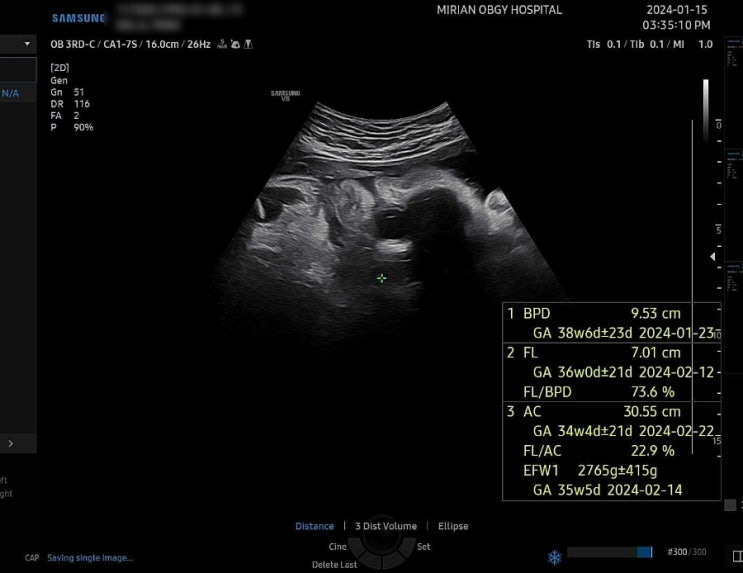

38주 0일차 하늘보는 아기 선택 제왕절개 예약

오늘은 38주 0일차 정기검진날 35주 4일차에 했던 막달검사부터 하늘보고 있다고 난산 가능성 언급하며 제...